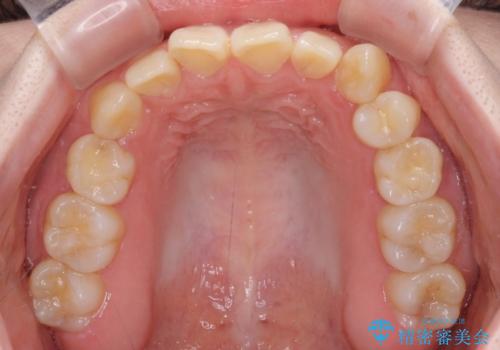

ディープバイトをインビザライン矯正で改善

- 前歯のデコボコと強い咬みしめを気にして来院された患者様です。

インビザラインを用いて、前歯の叢生を解消するとともに、ディープバイトを改善していくこととしました。

上顎に乳歯が左右1本ずつ残っていたため、若干咬み合わせに不具合が残りましたが、強い咬合力の原因であったディープバイトをしっかりと改善することができました。